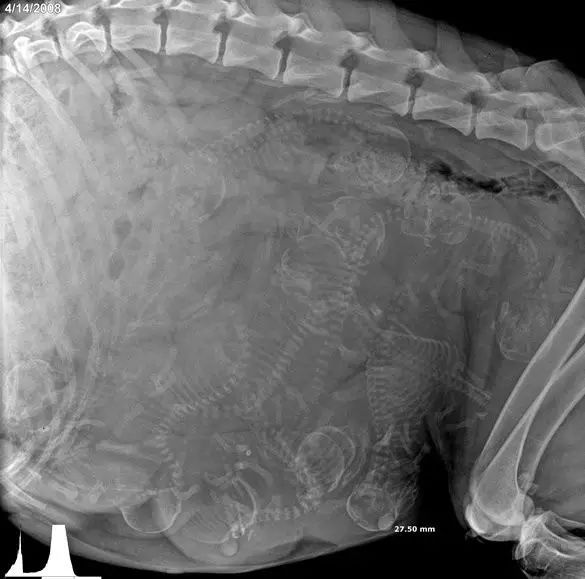

1. 狗狗。

能数得出是几胞胎吗?